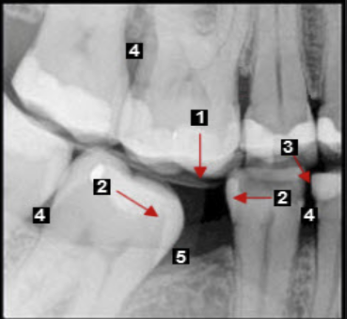

what are the numbers

alveolar bone

spongy (trabecular) bone

cortical plate

what are the arrows pointing to

lamina dura/cribriform plate